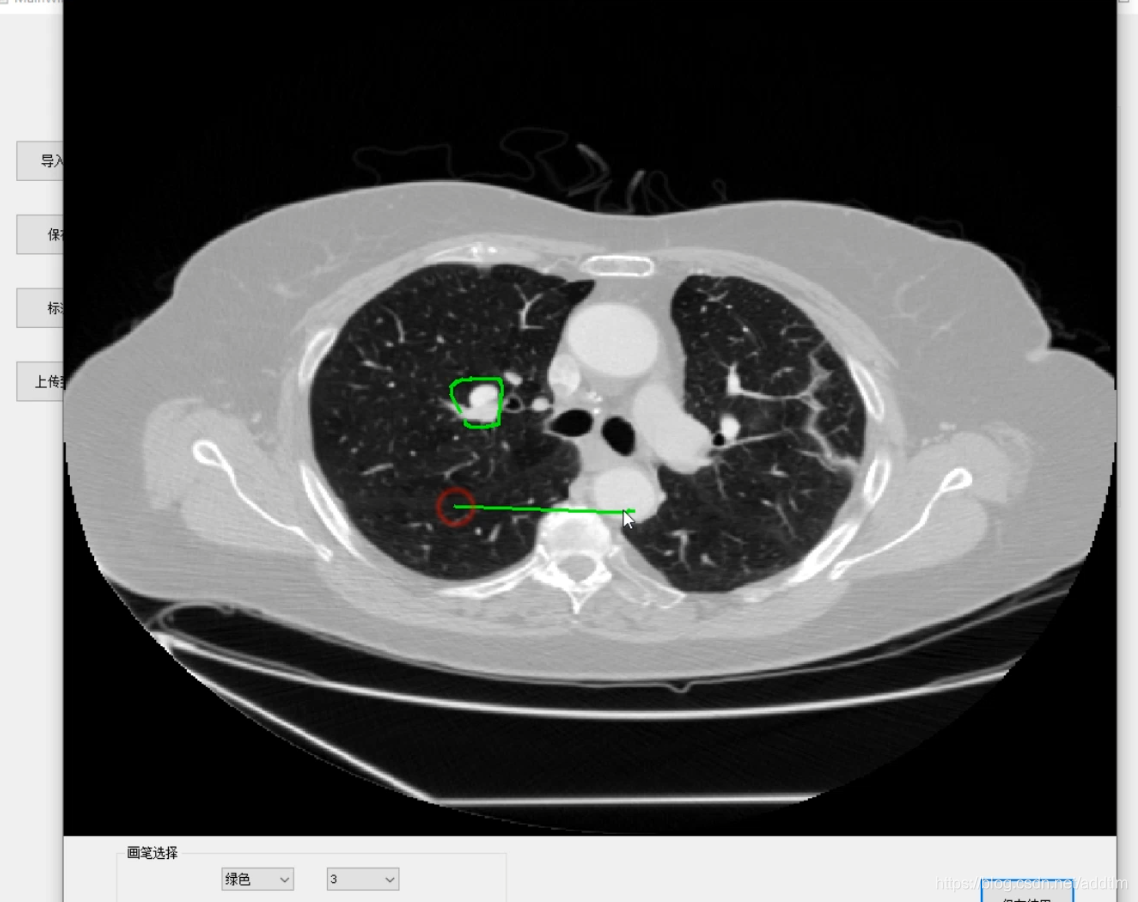

这两个网络训练达到一定的精度之后,就是GUI的设计和实现,我主要用了pyqt5和designer做了一个简单的界面。

GUI界面大致如下